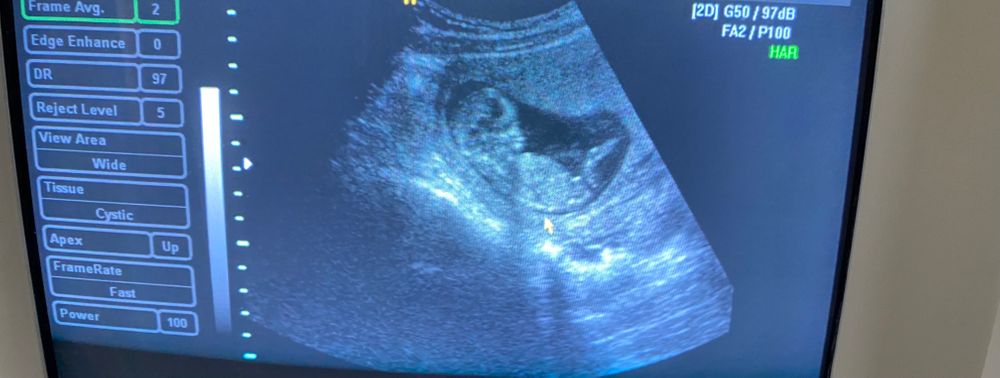

Может кто понимает ,подскажите больше на мальчика похож или же девочка

К сожалению срез (фотография) без необходимого элемента :)

Поэтому сказать о поле нельзя.

Удачи! На втором скрининге все раскроется!